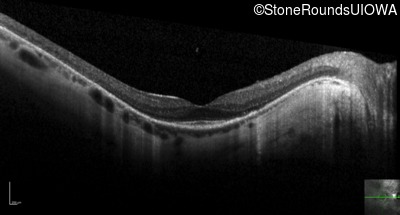

Optical Coherence Tomography - Right - 20/80 -1

Exemplar / OCT Stack

OCT Stack